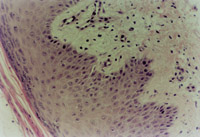

ÖÎÁÆ30Ììºó£¬£¬ £¬£¬£¬£¬£¬£¬´´ÃæÉÏÆ¤×éÖ¯ÔÙÉúÐÞ¸´ÓÅÒ죨ͼ5-3-5£©£¬£¬ £¬£¬£¬£¬£¬£¬Æ¤·ô½á¹¹ÒѾ­»ù±¾Õý³££¨Í¼5-3-6£© ¡£¡£¡£¡£¡£¡£ ¡£¡£

5-3-6 ÖÎÁÆ30ÌìºóµÄ´´ÃæÆä±íƤ×éÖ¯£¬£¬ £¬£¬£¬£¬£¬£¬ÕæÆ¤×éÖ¯½á¹¹ÒѳÊÐÄÀí״̬  HE¡Á20